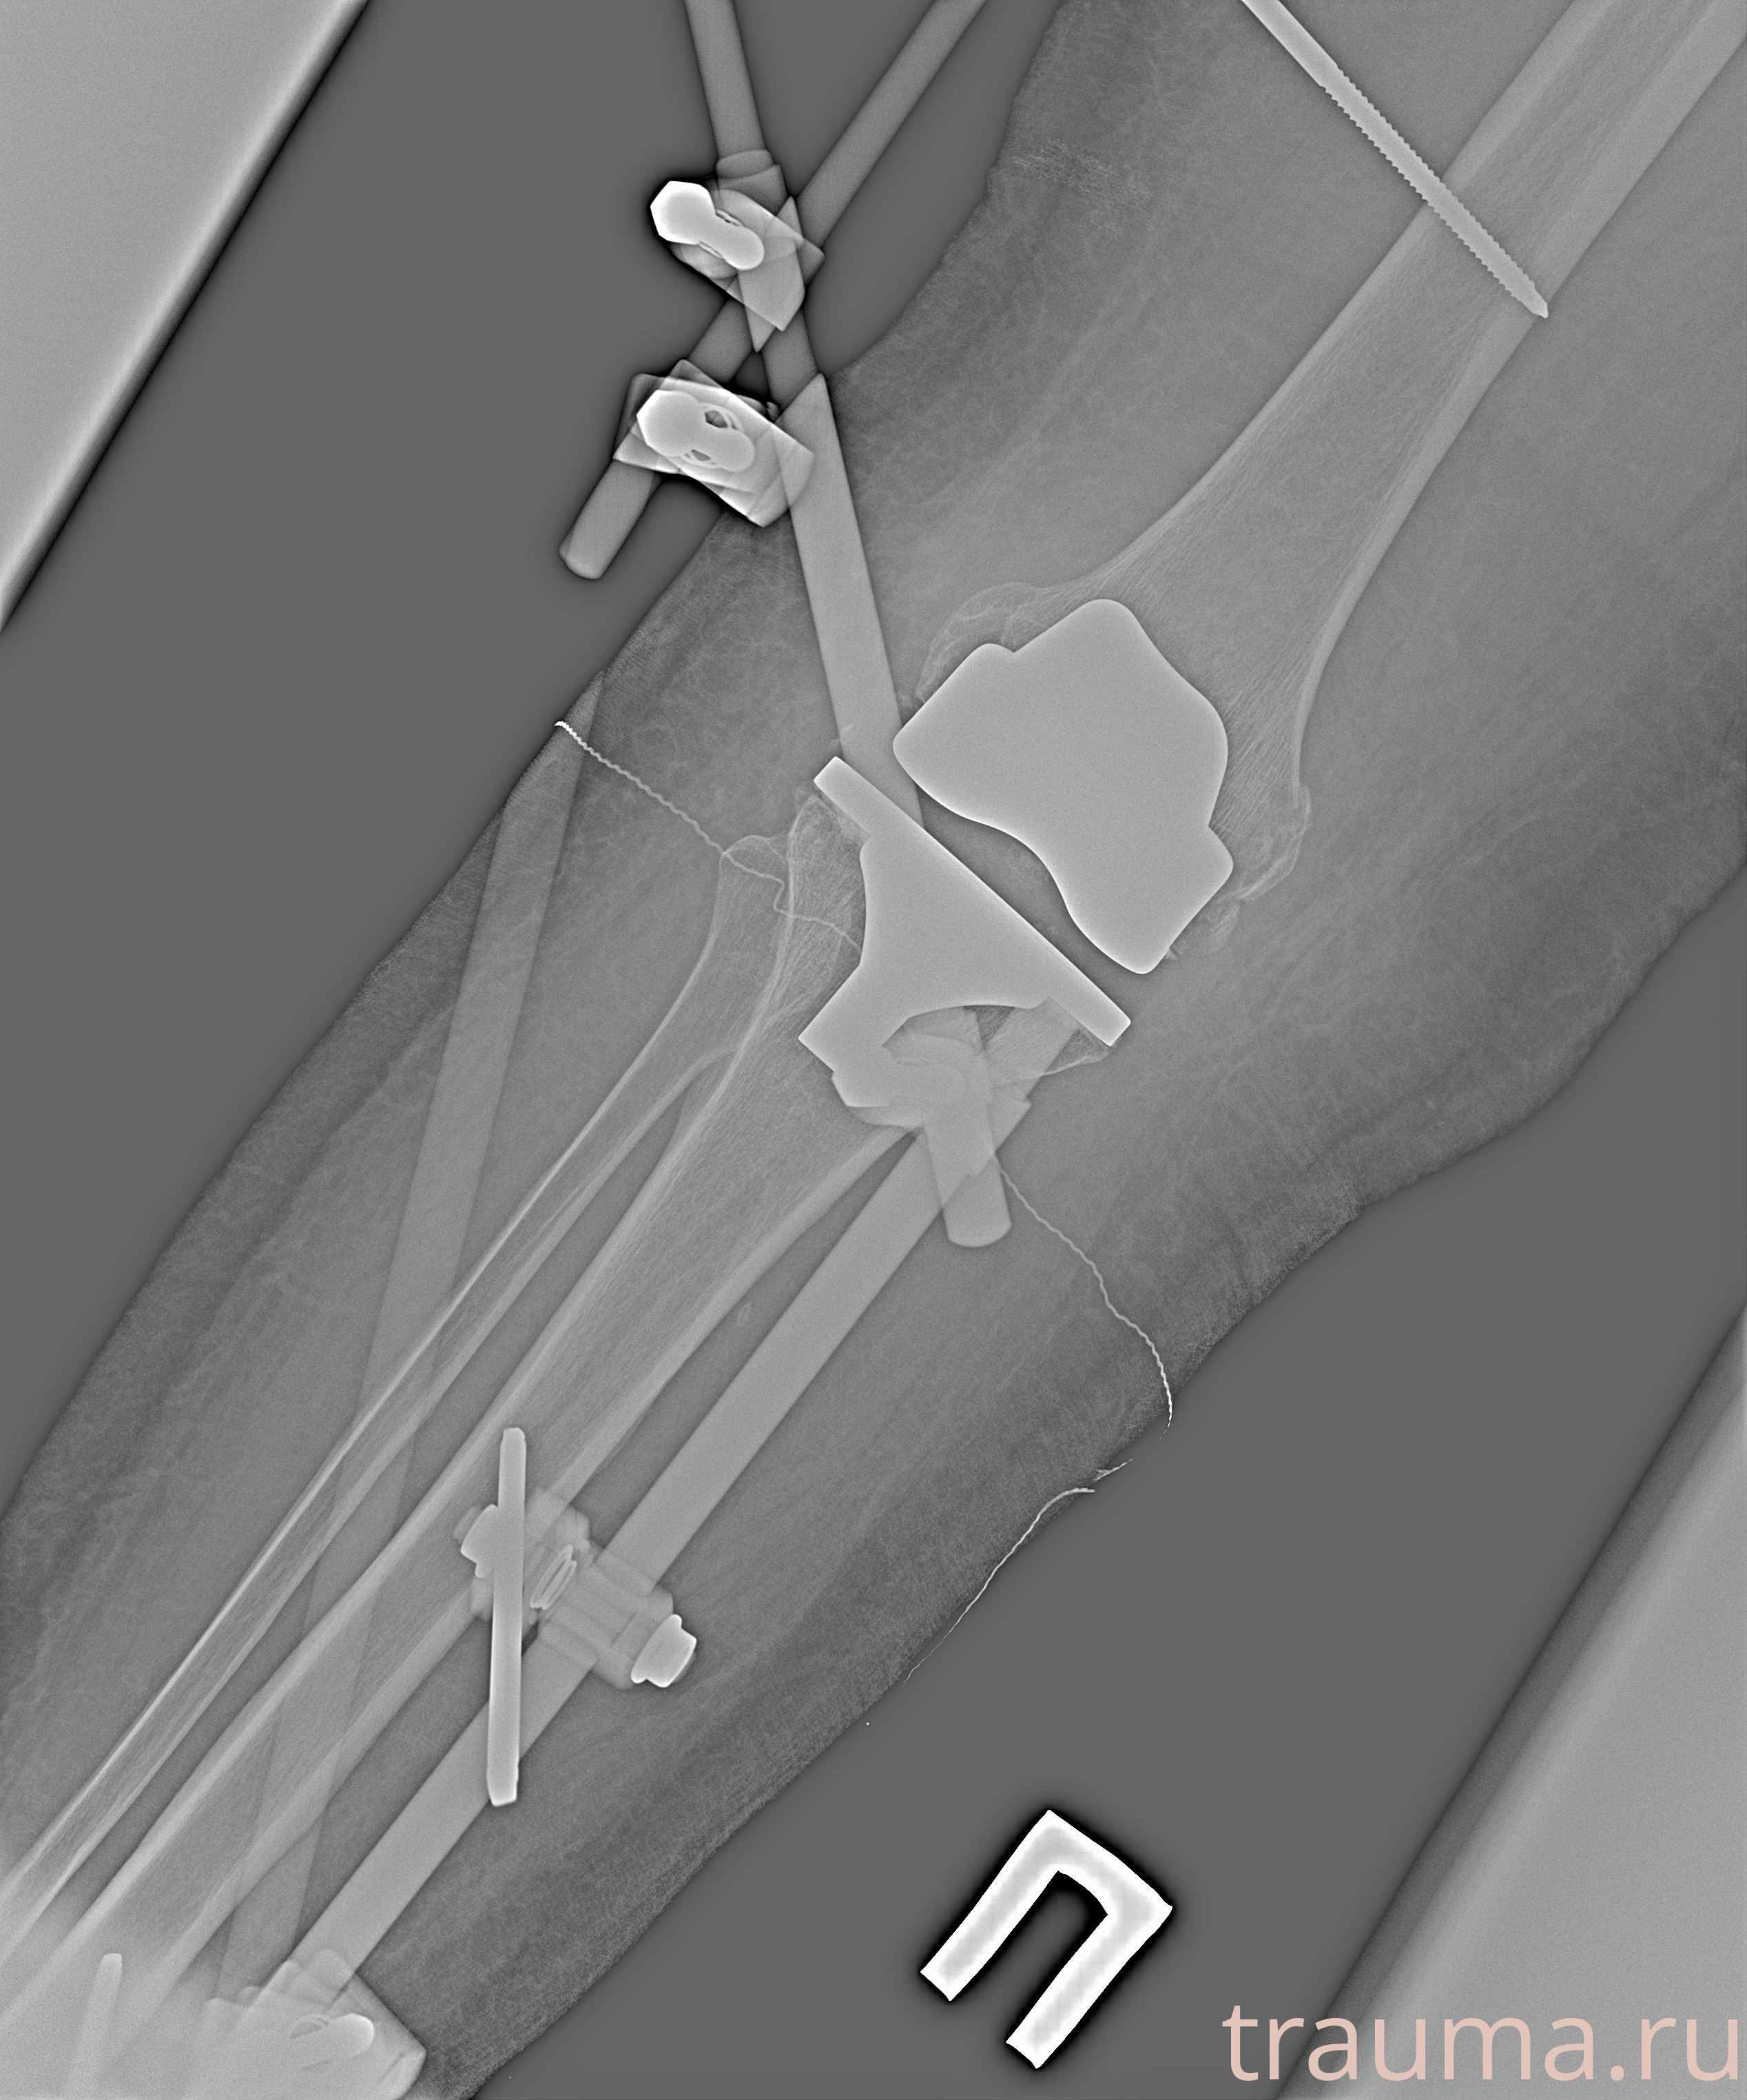

Рентген на дому: по вашему адресу приезжает врач-рентгенолог, травматолог-ортопед с мобильным рентгеновским аппаратом, проводит диагностику травмы или заболевания, делает необходимые рентгенограммы, дает рекомендации по дальнейшему лечению. Получить качественные снимки в домашних условиях возможно благодаря уникальной методике, разработанной МосРентген Центром для института  Склифосовского